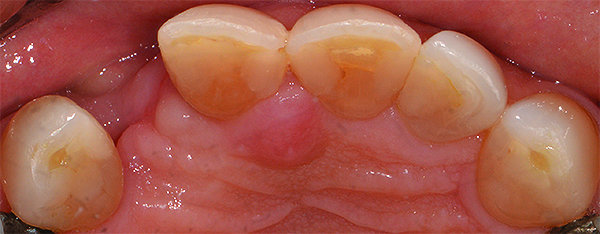

(2.) A patient presented with a missing lateral incisor. The patient was treatment planned to receive a fixed dental prosthesis retained by the adjacent central incisor and canine.

Figure 2